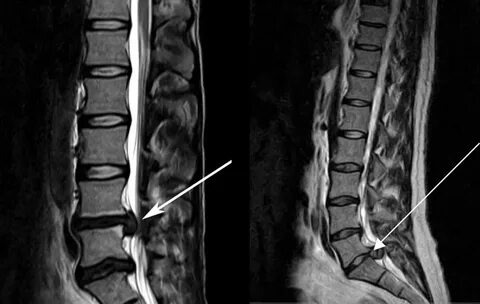

Грыжи🥹